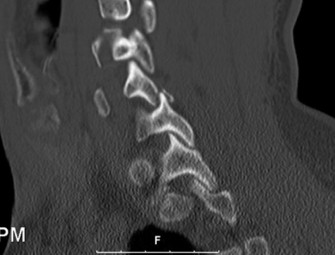

CASE 1 A 63-year-old male sustained a hyperextension injury to his neck while diving into a pool. Upon presentation, he reports decreased sensation in his hands and decreased strength in his arms and wrists, but no lower extremity complaints. On motor examination, he has 5/5 strength in his deltoids and elbow flexors and 4/5 strength in the elbow extensors, wrist extensors, and finger flexors. Lower extremity motor examination is normal. Sensation is decreased to light touch in both hands. Otherwise his sensation is preserved. Images of his cervical spine are shown in Figures 1–1 to 1–3.

Figure 1–3

The correct answer is (B). The clinical scenario describes a patient with central cord syndrome (CCS). CCS continues to be the most common incomplete spinal cord injury accounting for 15.7% to 25% of all spinal cord injuries. The characteristic presentation is an extension moment injury in a previously spondylotic and stenotic spine. Figures 1–1 to 1–3 demonstrate a spondylotic spine with central narrowing and CSF effacement that is worst at the C3–4 level. Bleeding, edema, and/or Wallerian degeneration lead to damage of the lateral corticospinal tract which is the main descending motor tract in the spinal cord. The more central anatomic position of the homunculus to the upper extremities places them at greater risk than those to the lower extremities. As such, injury to the lateral corticospinal tract is characterized by upper more than lower extremity involvement and motor deficits being more pronounced than sensory deficits.